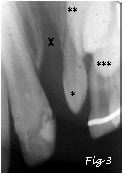

Sur la radiographie ci-dessous (Fig.3), on peut voir une fente alvéolaire (X) résiduelle, assez large, sans os (zone +sombre), entre l'incisive centrale et la latérale. On voit aussi l'incisive latérale*, de forme anormale conoïde. Canine** et prémolaire*** sont encore haut placées, au-dessus des dents de lait.

On notera enfin aussi, sur cette radiographie, l'ano-malie de la structure de l'émail de l'incisive centrale: il s'agit d'une hypoplasie de l'émail (cercle blanc, aussi sur Fig.4), autrement dit une anomalie de la minéralisation (calcification) de la couche superficielle de la dent (l'émail). Cette anomalie est fréquemment associée aux fentes alvéolaires (uni- ou bi-latérales).